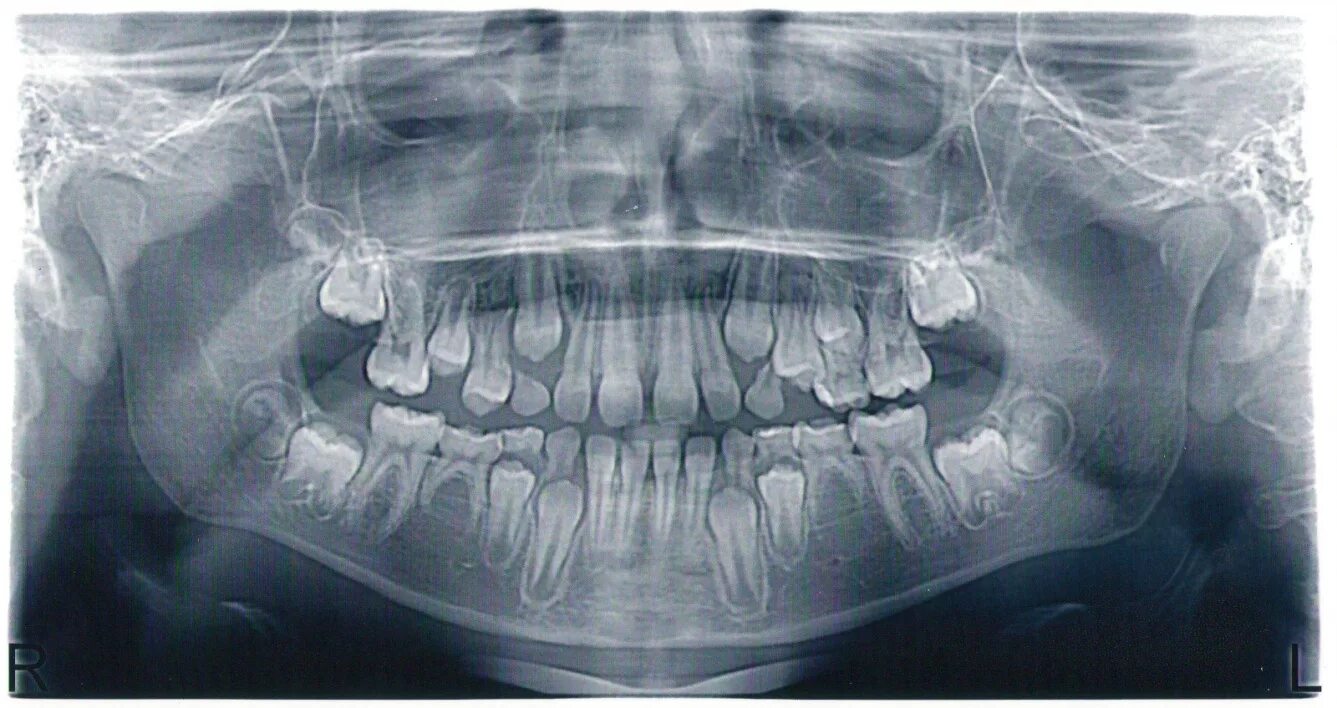

Снимок верхней и нижней челюсти